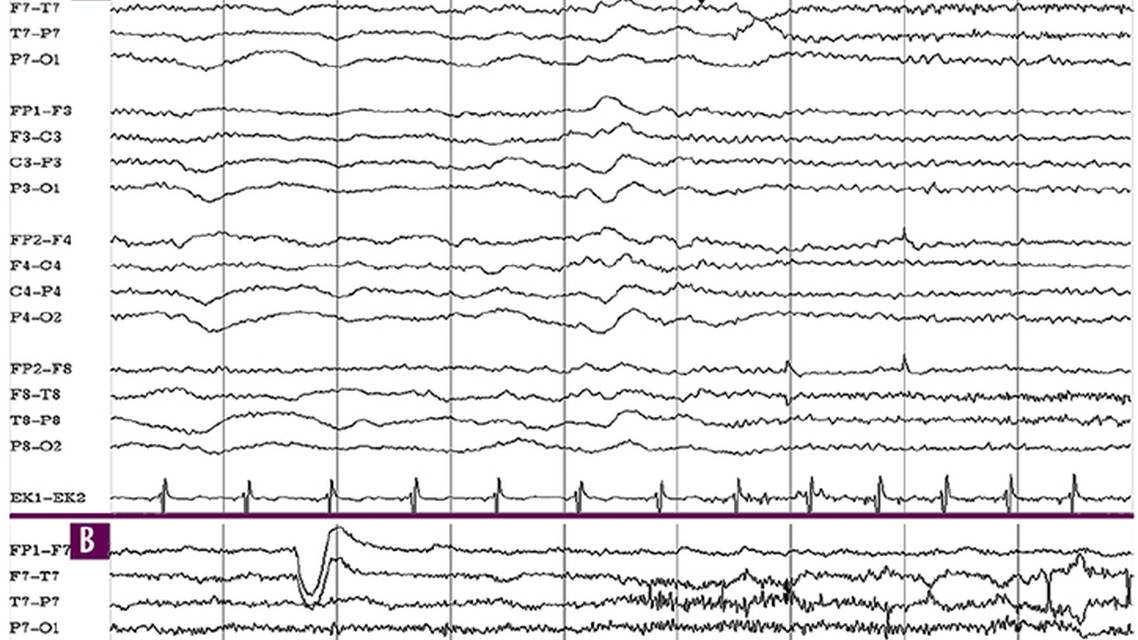

The ECG Recording

Every effort should be made to ensure that the electrocardiogram (ECG) channel in the EEG recording montage is recording properly. The ECG is invaluable in recognizing cardiac-related artifacts; determining seizure occurrence, even when the EEG is indeterminate; and diagnosing potentially fatal cardiac events.28 It is not uncommon for ictal tachycardia to be the only convincing objective evidence of an epileptic mechanism, because an EEG discharge may not be observable, often because of muscle and movement artifacts from the clinical seizure activity. The degree of tachycardia that suggests an epileptic mechanism in focal seizures with impaired awareness is 120% to 218% of baseline heart rate but only 84% to 126% during nonconvulsive PNES.29 Heart rate during epileptic convulsive seizures is 136% to 236% of baseline heart rate, compared with 101% to 137% during convulsive PNES. These findings alone are not very useful clinically because of overlap in the values. A derivation from these findings, however, that heart rate increases of at least 1.5 times above baseline are highly sensitive and specific for an epileptic seizure mechanism, strongly indicates an epileptic explanation for the spell. Ictal tachycardia is also characteristically abrupt in onset,30 and often precedes seizure onset on EEG.31 Figure 1 demonstrates diagnosis of epileptic seizures and treatment with antiseizure medication based on EEG and ECG findings when EEG seizure discharges are undetectable.